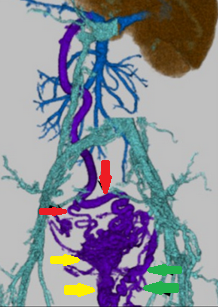

Κόκκινα βέλη: μαζική διάταση της δεξιάς ανώτερης ορθικής φλέβας. Παράπλευρη κυκλοφορία μεταξύ ανώτερων ορθικών φλεβών (κόκκινα βέλη) και ανορθικών κιρσών (κίτρινα και πράσινα βέλη) (Ευγενική παραχώρηση Dr. V. Penopoulos)